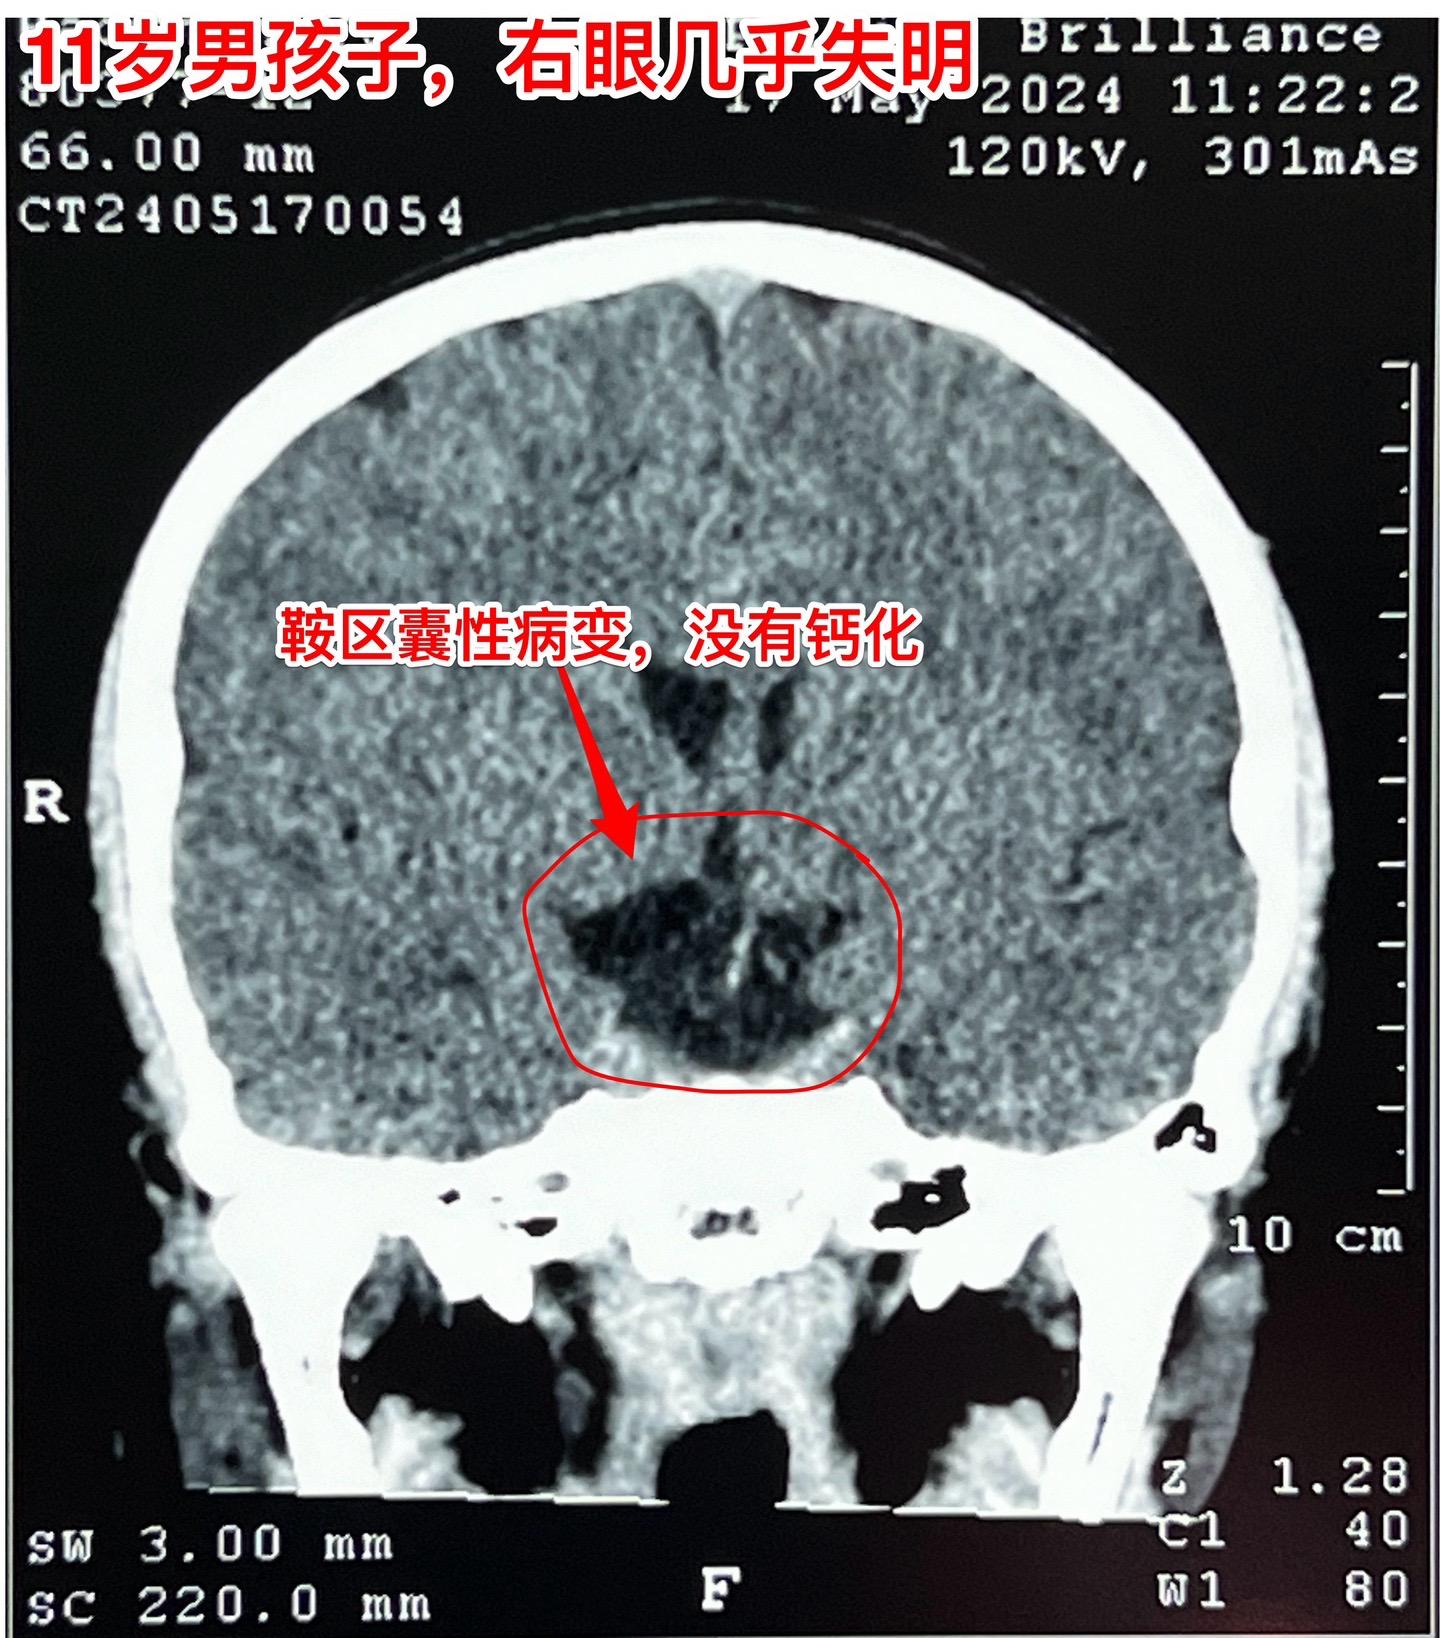

鞍区皮样囊肿比颅咽管瘤更罕见。11岁的湖北男孩子在学校体检查视力发现右眼几乎失明了,看不见东西,只有光感! 而他自己却不知道!平时也没有感到头痛,没有太多的不适。这个孩子是多粗心呀! 随后行脑部CT和磁共振检查发现鞍区 有个肿瘤,怀疑为颅咽管瘤。CT显示肿瘤没有钙化,这一点不符合颅咽管瘤。 5月31日作了开颅手术,将病灶完全切除。病灶的囊皮是灰色的,内部有油脂样的粘滞物,还含有毛发。所以术中诊断为皮样囊肿。这是近10年以来的第三例鞍区皮样囊肿手术。前两例